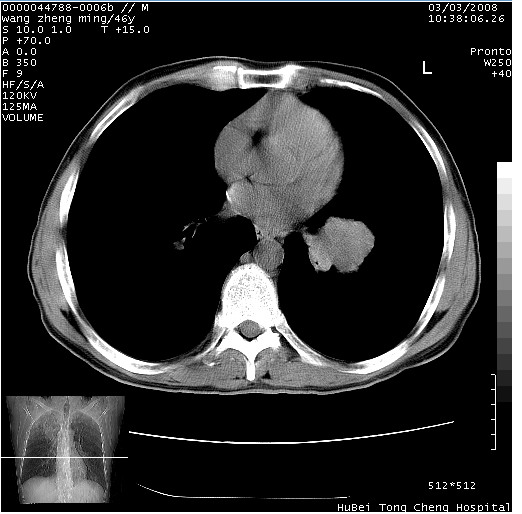

以下是引用卜一在2008-3-22 1:37:00的发言:[br]右肺实质性肿块,边缘不整,明显见毛刺征 分叶征及胸膜凹陷征,右上叶支气管明显变窄,远端散在的片状 斑片状实变影。另:左肺门较大肿块,支气管受累 变窄,远侧见阻塞性肺炎。纵隔内见肿大淋巴结。多考虑:右肺周围性肺癌伴左肺门 纵隔淋巴结转移!